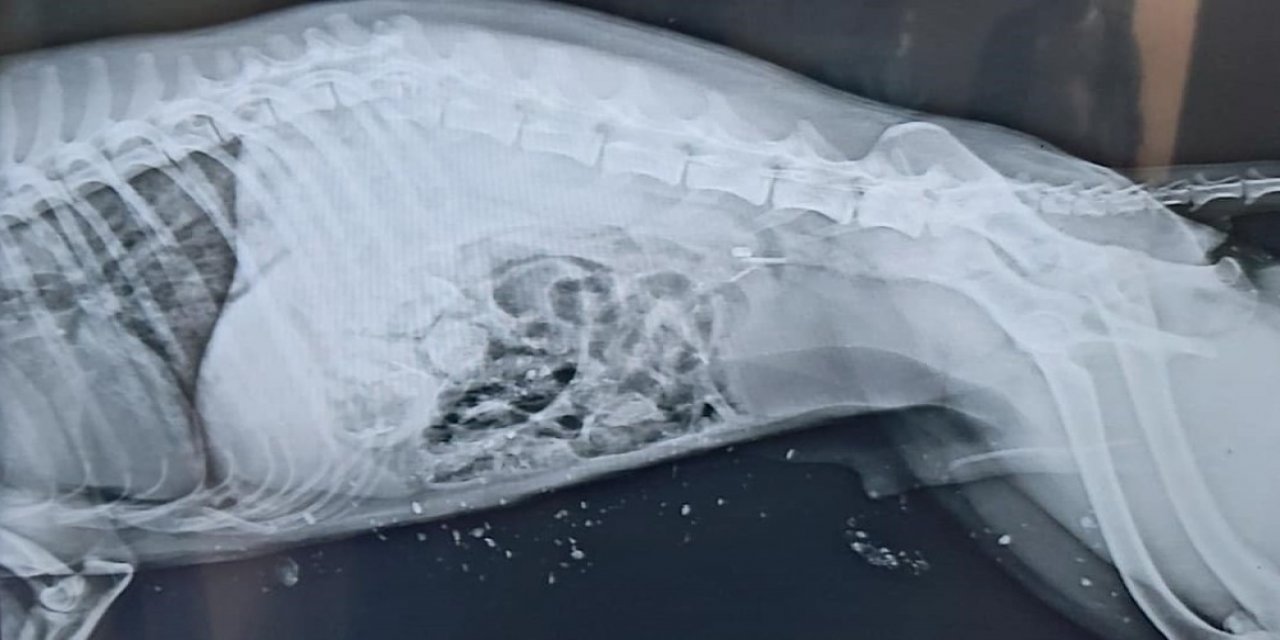

Edinilen bilgilere göre, Iğdır merkezde otoyol üzerinde bir aracın çarpması sonucu yaralanan Çakal'ı gören vatandaşlar ekiplere haber verdi. Haber verilmesi üzerine olay yerine gelen ekipler, ağır yaralı Çakal'a ilk müdahalesini yaparak hayvan barınağına götürdü. Daha sonra, Kafkas Üniversitesi Veteriner Fakültesi Hayvan Hastanesi Kliniğinde yapılan radyolojik muayenede, Çakal'ın omuriliğinin kırıldığı, ön bacaklarında parçalı kırık ve kanama olduğu, bu bulgulara bağlı olarak arka bacaklarının tutmadığı tespit edildi. Ağır yaralanan Çakal, Kafkas Üniversitesi Veterinerlik Fakültesi Hayvan Hastanesi'nde tedavi altına alındığı öğrenildi.